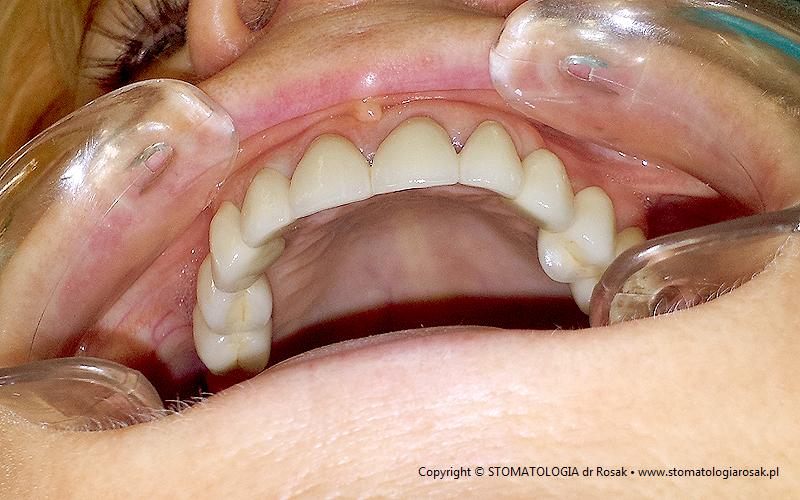

2b. Gotowe mosty pełnoceramiczne

na podbudowie cyrkonowej |

2c. Gotowe mosty i korony pełnoceramiczne

2d. Gotowa praca stała - korony pełnoceramiczne